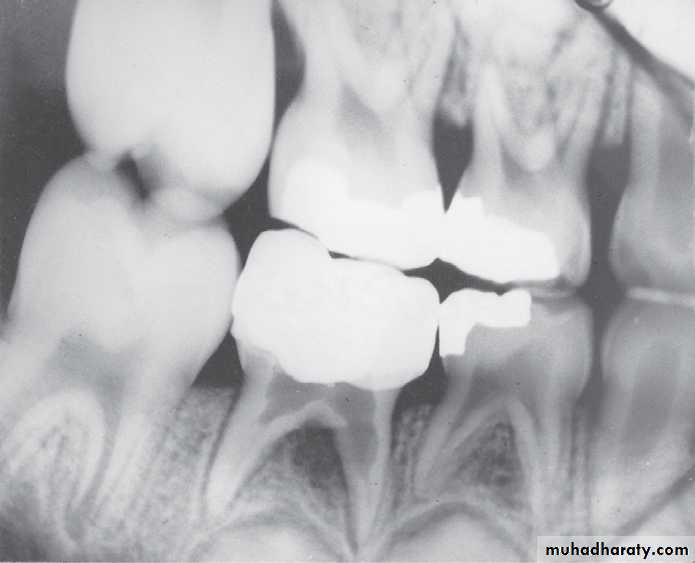

Deep caries in the first primary molar and due to that caries resorption in the bifurcation areaDeep caries in the mandibular second primary molar

Periapical radiographs

Infected mandibular second primary molar

has caused hypoplasia of the second premolar and delayed eruption of the tooth.Pre-eruptive “caries” on the crown of an

unerupted first premolar (arrow).